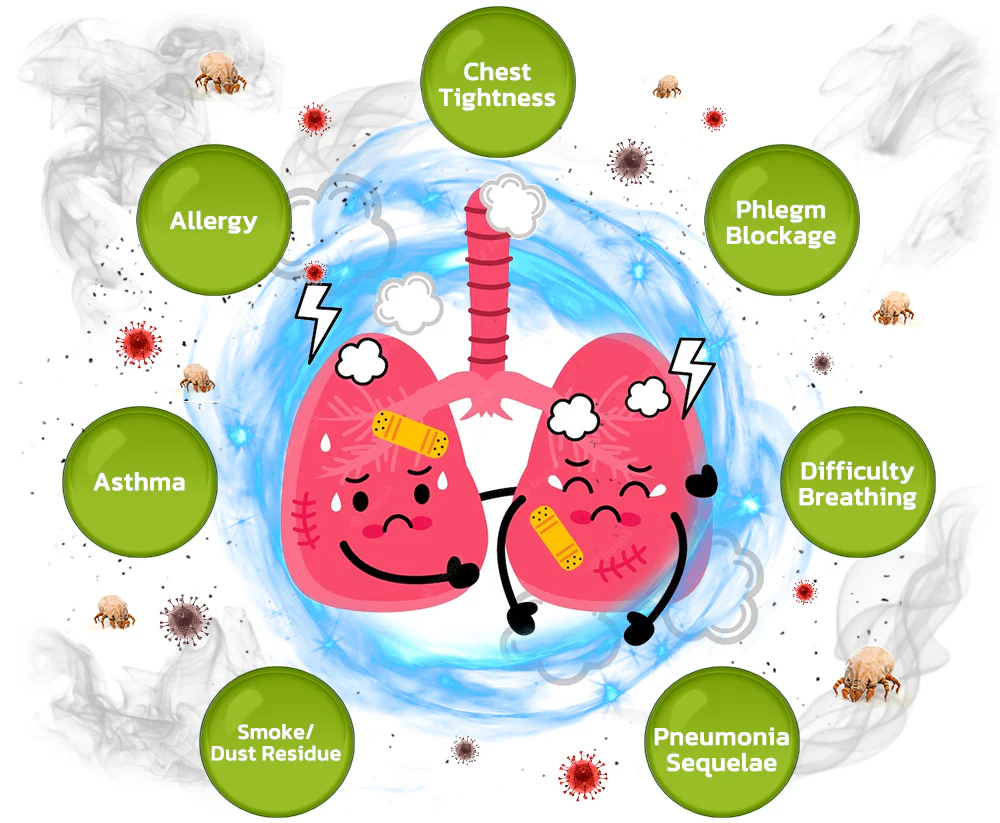

The HZA™️ BreathDetox Herbal Lung Cleansing Spray offers a convenient and effective solution for clearing mucus and waste from the lungs, as well as purifying and cleansing the upper respiratory passages. It is specifically designed to repair damage caused by allergies, asthma, dust, and smoking within a span of 8 weeks. This innovative product provides individuals with weakened respiratory systems an effortless opportunity to restore their breathing capacity.

【Expert】Organic Herbal Fusion – Purify trachea and lungs by eliminating lingering buildup – Restore optimal functionality of alveoli – Regenerate tracheal tissue – Alleviate allergies and asthma symptoms – Enhance the sensation of unobstructed breathing – Provide support for individuals with COPD

Clinical trials and surveys have yielded compelling evidence supporting the effectiveness of this medication in the treatment of chronic pharyngitis, pulmonary nodules, and pulmonary dysfunction. Furthermore, it has demonstrated notable efficacy in managing environmental allergies and asthma. Additionally, thorough verification has established the significant role of the spray in both treating and preventing the consequences of pulmonary inflammation. These findings contribute to the growing body of evidence highlighting the medication’s effectiveness across a range of respiratory conditions.